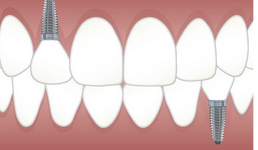

임플란트 가격 시술과정 등 정보에 대하여 조사하도록 하겠습니다. 임플란트는 손상된 이빨이나 빈 이빨을 대체하기 위한 인공 이빨입니다. 기본적으로 작은 나사 모양의 금속 장치로, 잇몸과 안면골 사이에 삽입됩니다. 이 장치는 실제 이빨과 동일한 역할을 수행하고, 씹기, 말하기 및 미소를 지을 때 부드러운 모습을 유지합니다.

임플란트의 주요 재료는 티타늄이며, 이는 몸에 큰 탈이 없는 재료입니다. 티타늄 재질은 뼈와 잘 결합되어 안정성을 높이며, 인공 이빨을 장기간 활용할 수 있도록 해줍니다.

임플란트 수술은 전문적인 치과 의사나 구강 외과 전문의에 의해 수행됩니다. 기본적으로 수술 후 임플란트는 몇 개월 동안 치아와 함께 인공 잇몸으로 덮여 골이 잘 결합되도록 하고, 그 후에 인공 이빨이 부착됩니다.

- 임플란트 삽입: 치과 의사는 임플란트를 안정적으로 삽입하기 위해 잇몸을 절개하고, 임플란트를 치아 뼈에 삽입합니다. 수술 후에는 굳게 고여있는 결손을 채우기 위해 뼈 이식이 필요한 경우도 있습니다.